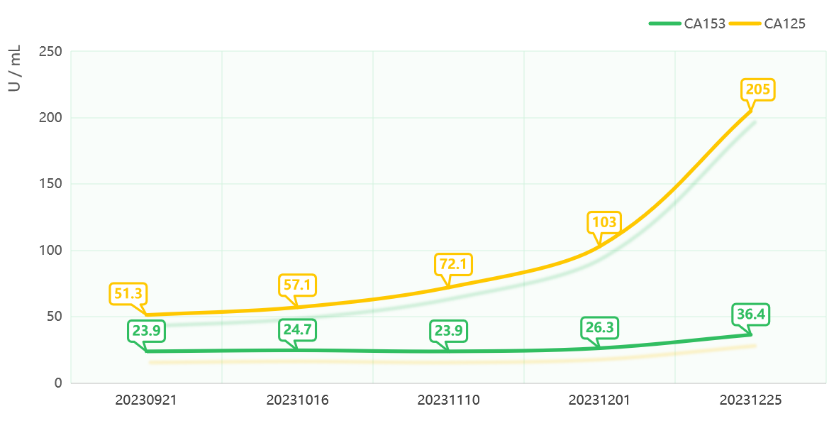

治疗期间规律随访肿瘤标志物水平,CA153及CA125均有明显降低。

2023-04-26至2023-09-21治疗期间肿瘤标志物变化

治疗期间规律随访肿瘤标志物水平,CA153相对稳定,CA125呈升高趋势。

本例患者在治疗过程中因免疫相关心肌炎选择暂停免疫治疗,后期使用维迪西妥单抗单药治疗。在前后共13周期、长达8月余的治疗过程中,患者病情稳定,多发转移病灶的进展得到了有效控制。联合治疗期间影像学检查提示病灶缩小,疗效评估为SD且肿瘤标志物CA153及CA125均明显降低,治疗方案在控制肿瘤进展方面取得了一定成效。单药治疗期间影像学检查提示病灶稍增大,但整体疗效仍维持SD,肿瘤标志物CA153相对稳定,CA125呈升高趋势,病情处于相对稳定状态。从该例患者的治疗过程来看,维迪西妥单抗可能为HER2阳性腮腺癌患者带来长期的临床获益,此外,即使在PD-L1表达水平不高的情况下(本例患者CPS<1),维迪西妥单抗联合免疫治疗仍能进一步提升疗效。在联合用药过程中,需要密切监测免疫相关心肌炎、肝炎、肺炎、皮炎、甲状腺功能异常等免疫相关不良事件(irAEs)的发生,并依据严重程度给予及时处理。